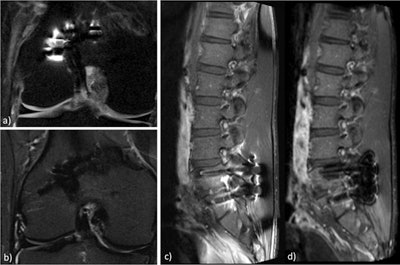

Speaking from experience, Brandão pointed to cardiac MRI, which relies on fast imaging and patient cooperation. Cine imaging is usually made with steady-state free precession (SSFP) pulse sequences, which are prone to susceptibility effects arising from lung-heart interfaces, or in patients with pleural effusion. The heterogeneity of the main field leads to local variations of the SSFP signal and dark-band artifacts.

"There are possible solutions to this problem. These include ensuring the lowest possible repetition time, performing localized high-order shimming to reduce those steady-state signal dropouts, and performing the frequency scout to identify the frequency offset to further minimize these artifacts. That said, the use of spoiled gradient-recalled echo (GRE) sequences instead of SSFP may be the ultimate alternative to get good-quality images," she said.